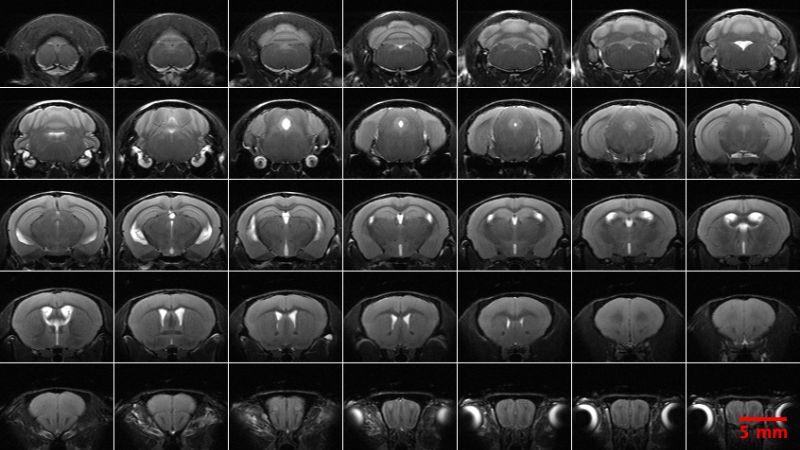

NBP Pre-pulse Inhibition/Startle Reflex | PCI MRI-Anatomical |

NBP Rotarod | PCI MRI-Angiography |

NBP Social Approach (3-Chamber) | PCI MRI-Diffusion Tensor Imaging |

NBP Spontaneous Alternation-Visual Cues (Y-Maze) | PCI MRI-Diffusion Weighted Imaging, Isotropic |

NBP Tail Withdrawal | PCI MRI-Neurite Orientation Dispersion and Density Imaging |

NBP Von Frey | PCI MRI-Neuroanatomical |

PCP Auditory Brainstem Response | PCI MRI-Neuroanatomical, Isotropic |

PCP Blood Pressure, Non-Invasive | PCI MRI-Resting State Functional (rsfMRI) |

PCP Direct & Indirect Ophthalmic Exam | PCI MRI-rsfMRI, Isotropic (imaging acquisition only) |

PCP Distortion Product Otoacoustic Emission | PCI MRI Susceptibility Weighted Imaging |

PCP DSI Telemetry Cardiovascular Blood Pressure | PCI MRI-T2star Mapping, Isotropic |